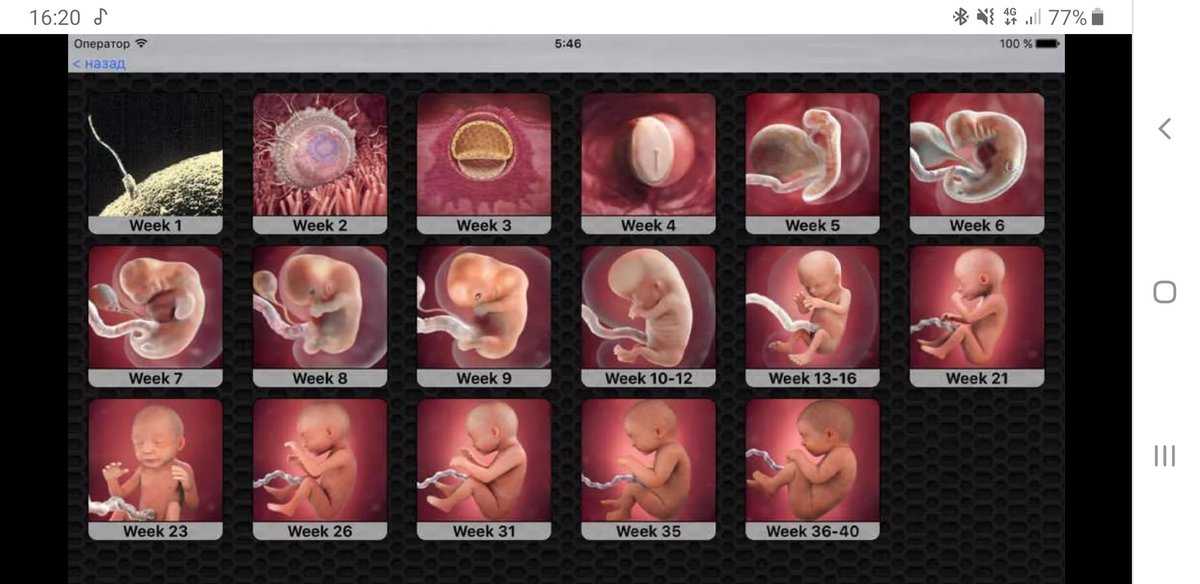

Фотография Плода В Животе

Фотография Плода В Животе 113 фотографий